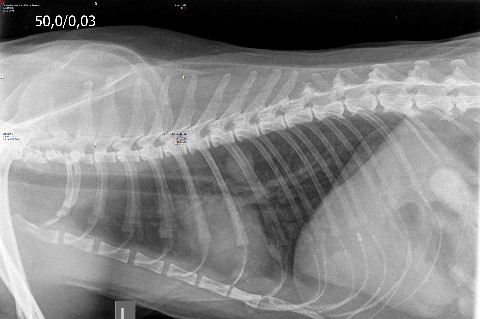

Lungenerkrankungen

Erkrankungen der Lunge und der oberen Atemwege können verschiedene Ursachen haben. Deshalb bemühen wir uns stets eine Diagnose zu stellen, die eine exakte Therapie ermöglicht. Neben Röntgen und Endoskopie helfen uns zum Auffinden von Infektionen, Allergien, Asthma, Ergüssen oder Tumoren auch labordiagnostische Untersuchungen wie die Blutgasanalyse oder die parasitologische Untersuchung, beispielsweise auf Lungen- oder Herzwürmer.